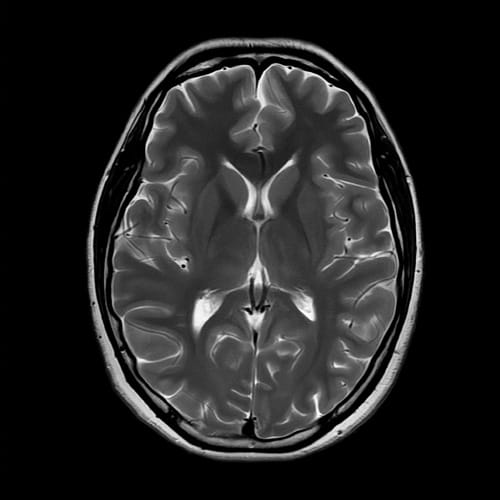

脳MRI

脳の断面を撮影し、無症候性脳梗塞や脳出血、脳腫瘍などの有無を調べます。

症状がない段階の小さな異常も早期に発見できる可能性があります。